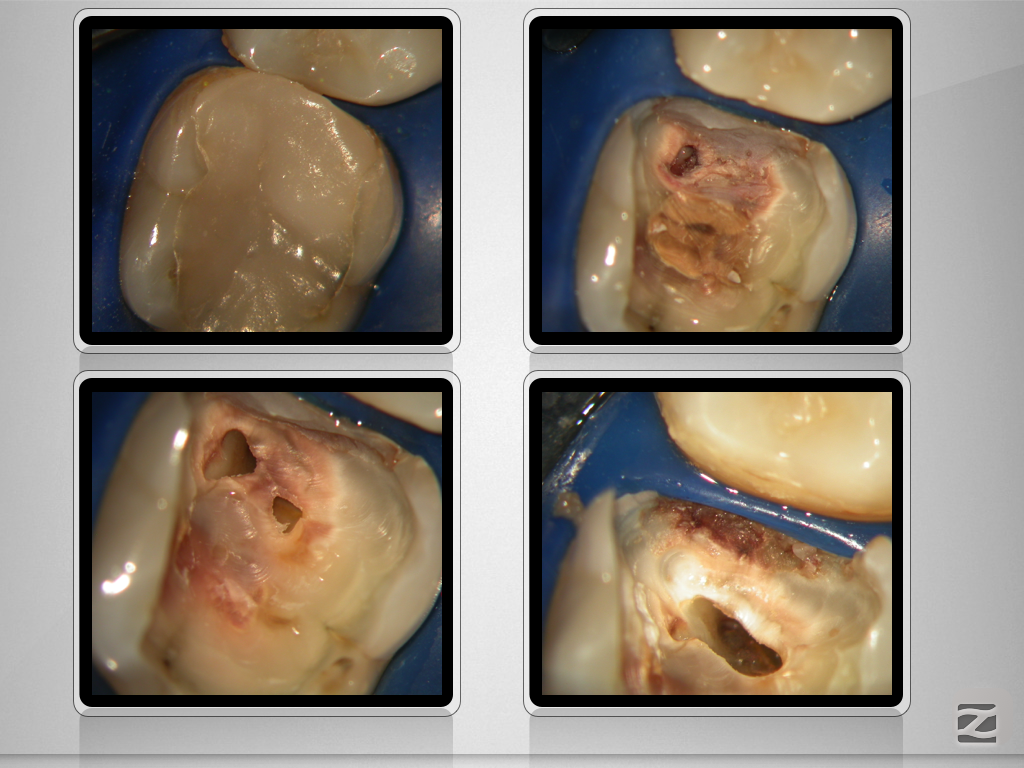

46D.002

Partielle Pulpanekrose